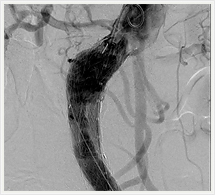

画像紹介(ステントグラフト編)

ステントグラフトは、人体に馴染みやすい人工布を筒状に形成し、これにステントといわれるバネ状の金属を縫い付けた人工血管で、これをストロー状のチューブで、患者さんの太ももの付け根から動脈内に挿入します。ステントグラフトを動脈瘤のある部位まで進め動脈瘤の内側ステントグラフトを挿入します。そうすることで動脈瘤の拡大を抑え、動脈瘤が拡大しなければ破裂する危険性がなくなります。このように、ステントグラフトによる治療は外科手術に比べて切開部が小さく、身体への負担が極めて少ない低侵襲血管内治療です。

ステントグラフト挿入術直後の造影

(上部)

(下部)